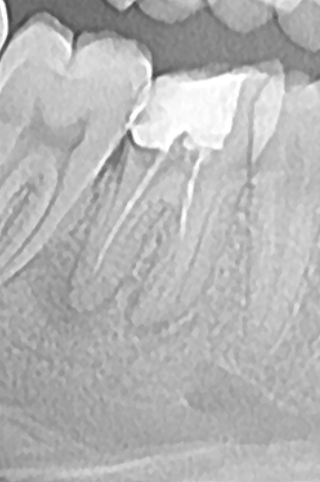

Mulți dintre dinții tratați sau retratați, sunt infectați sau prezintă o leziune inflamatorie periapicală (Fig. 4.9.6), de aceea evoluția cazului spre succes depinde foarte mult de îndepărtarea microorganismelor din sistemul canalar. Irigarea copioasă ne ajută, mai ales în cazul canalelor curbe și pentru a evidenția, curăța și obtura și anumite canale secundare ce sunt blocate de resturi dentinare (Fig. 4.9.7). Astfel, se reduce flora microbiană din sistemul canalar și din țesuturile adiacente favorizând vindecarea osoasă, situație observată după 6 luni în acest caz. (Fig. 4.9.8)